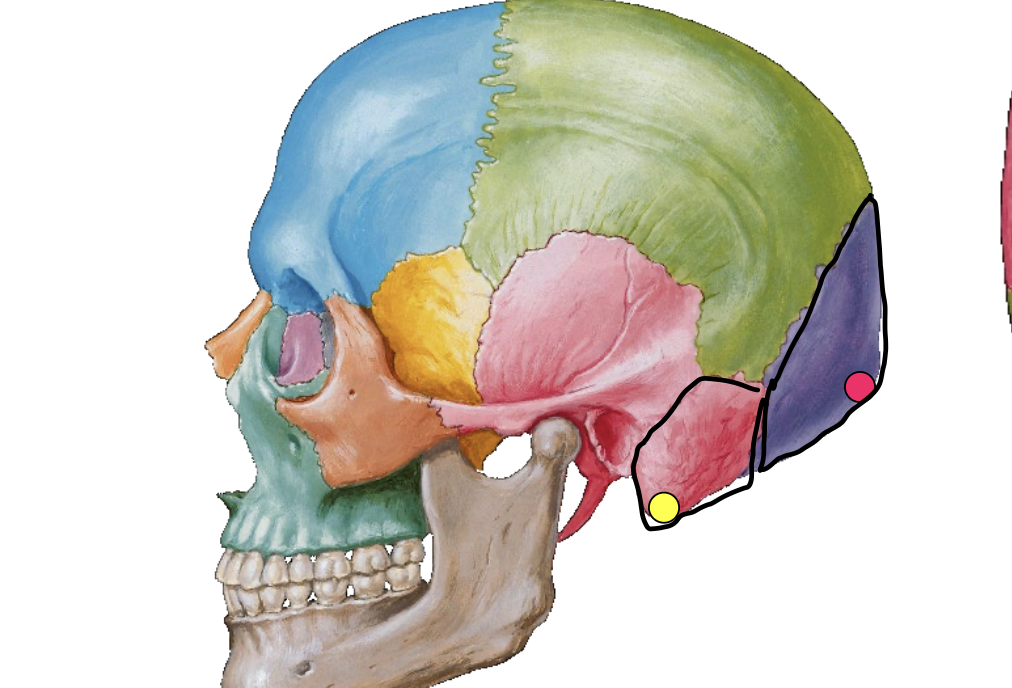

What is the pink dot locating in this image?

External occipital protuberance

What is the yellow dot locating in this image?

Mastoid process